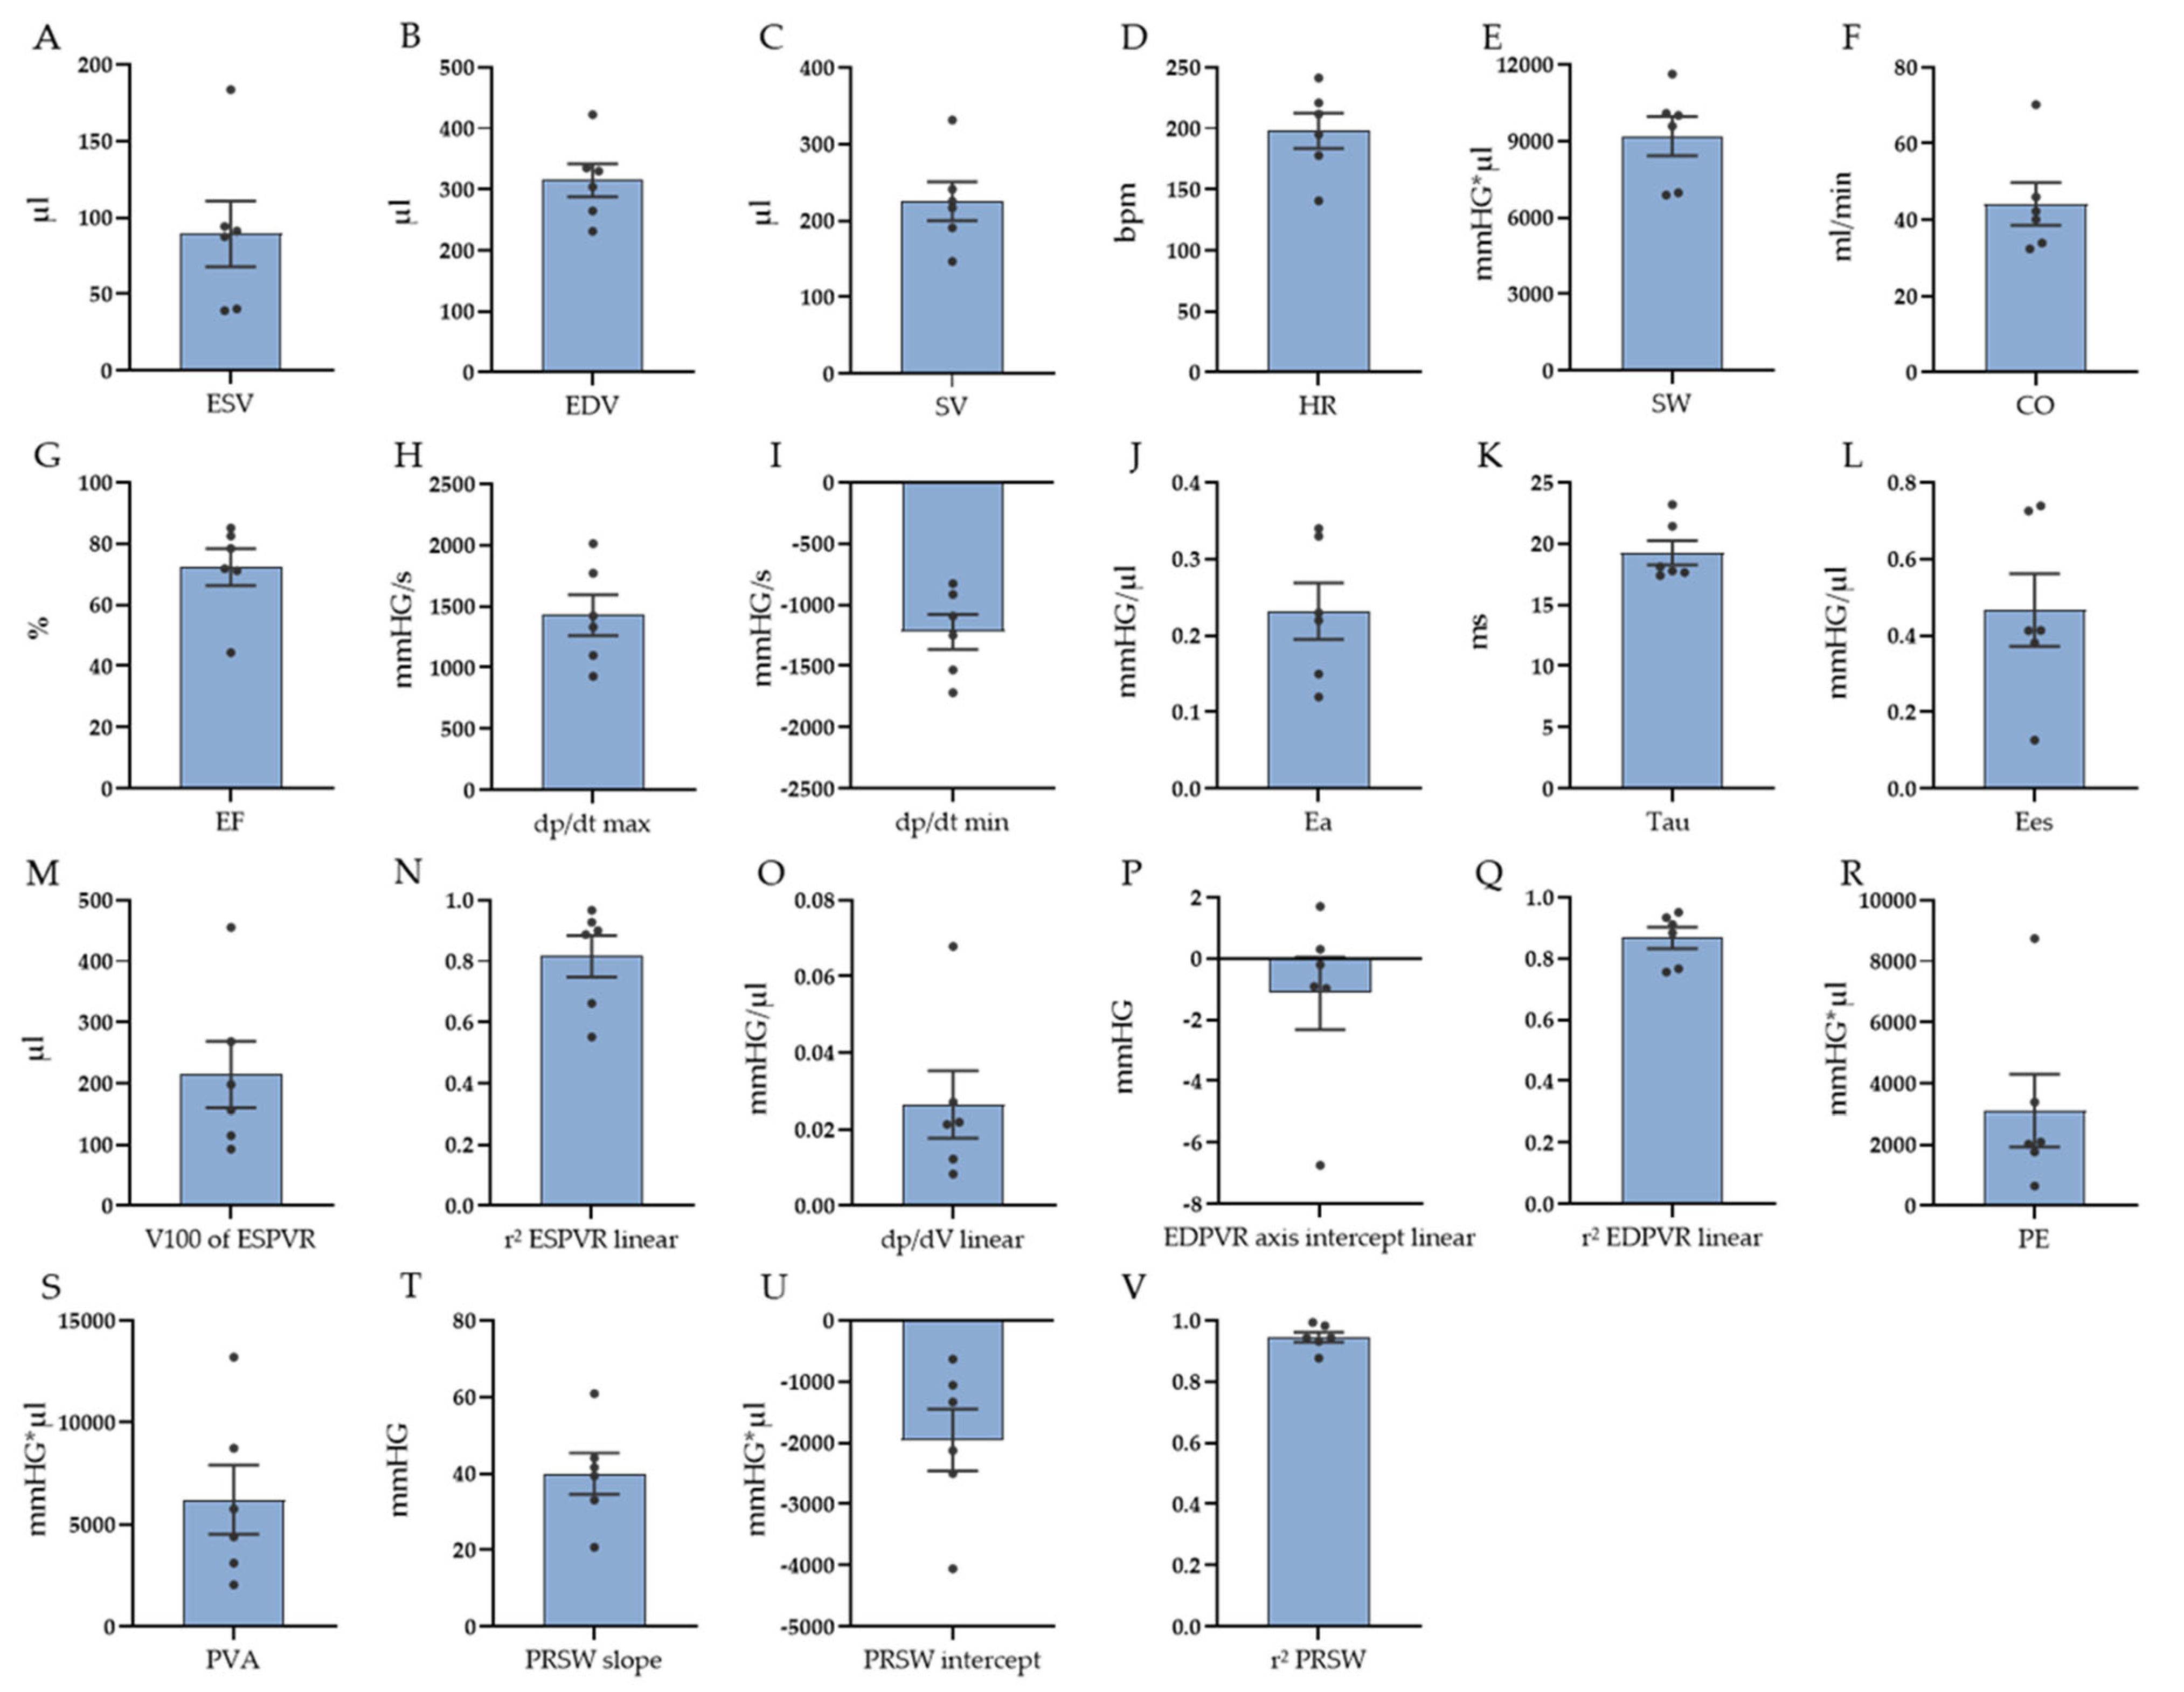

3.1. PV Loop Measurements

| Parameter | Mean ± SEM (n = 6) | |

| Baseline data | ||

| HR (bpm) | 198 ± 14 | |

| ESV (µL) | 89 ± 21 | |

| EDV (µL) | 315 ± 27 | |

| SV (µL) | 226 ± 25 | |

| EF (%) | 72 ± 6 | |

| CO (ml/min) | 44 ± 6 | |

| SW (mmHG∗µL) | 9191 ± 768 | |

| dp/dt max (mmHG/s) | 1429 ± 166 | |

| dp/dt min (mmHG/s) | −1221 ± 142 | |

| Ea (mmHG/µL) | 0.23 ± 0.03 | |

| Tau (ms) | 19 ± 1.0 | |

| Contractility | ||

| ESPVR (linear) Ees (mmHG/µL) | 0.467 ± 0.095 | |

| ESPVR (linear) V100 (µL) | 214 ± 55 | |

| ESPVR (linear) r2 | 0.816 ± 0.069 | |

| ESPVR (quadratic) a | −0.012 ± 0.004 | |

| ESPVR (quadratic) b | 1.634 ± 0.494 | |

| ESPVR (quadratic) r2 | 0.857 ± 0.048 | |

| PRSW r2 | 0.945 ± 0.017 | |

| PRSW slope | 40 ± 5 | |

| PRSW axis intercept | −1949 ± 506 | |

| PE mmHG∗µL | 3112 ± 1181 | |

| PVA mmHG∗µL | 6217 ± 1689 | |

| Compliance | ||

| EDPVR (linear) dp/dV (mmHG/µL) | 0.027 ± 0.009 | |

| EDPVR (linear) axis intercept | −1.132 ± 1.189 | |

| EDPVR (linear) r2 | 0.867 ± 0.035 | |

| EDPVR (exponential) dp/dV (k1) (mmHG/µL) | 0.013 ± 0.004 | |

| EDPVR (exponential) k2 | 0.793 ± 0.292 | |

| EDPVR (exponential) r2 | 0.843 ± 0.039 |